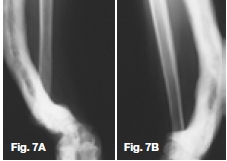

Figures 1, 2, & 3 show a mixed radiolucent/opaque lesion affecting the maxilla, crossing the midline in an edentulous patient, causing flattening of the palate. A lateral skull radiograph of another patient (Fig. 4) shows osteoporosis imperfecta in the posterior and anterior parts of the skull (green arrows) along with thickening of the calvarium and cranial vault which are cardinal radiological signs of the condition. Figures 5 & 6 illustrate "cotton wool" radio-opacities in the skull and the base of the skull shows dense sclerosis. All the images mentioned so far are typical features of Paget's disease. Sir James Paget, surgeon and pathologist who is best remembered for naming Paget's disease. The disease is idiopathic and can be divided into three stages: initial bone resorptive phase, vascular phase with osteoblastic repair, and approximal/ sclerosing phase. The jaws are involved in approximately one in Ave cases, with the maxilla being affected about twice as frequently as the mandible. During the initial phase of bone resorption, the affected bones may be deformed or painful, particularly the weight-bearing structures such as the long bones of the legs (Fig. 7A & B). Later the affected bones expand, commonly in the maxilla, mandible or cranium. At this stage, the dental patient who wears full dentures may complain that the fit of the dentures is becoming progressively poorer. When the maxilla is affected, the alveolar ridge widens and the palatal vault can flatten (Fig. 2). When teeth are present, they may become increasingly spaced, with extensive jaw enlargement. Neurologic complaints can result from increased deposition of bone in the areas of the foramina of the skull causing headaches, auditory disorders progressing to deafness, visual disorders progressing to blindness, facial paresis, and vertigo. The bones are relatively brittle; hence, fractures are likely. Generalised radiolucency/osteoporosis intermediate stage with mixed radiolucency/radiopacity, "driven snow" coarse trabeculation, "cotton wool" radio-opacities in the final stage (Figs. 5 & 6). Hypercementosis, loss of lamina dura, obliteration of the periodontal ligament spaces (Fig. 8) and external root resorption (Fig. 9) may also be present. The upper hand wrist radiograph (Fig.10) of another patient shows the disease affecting the phalanx of the third digit.